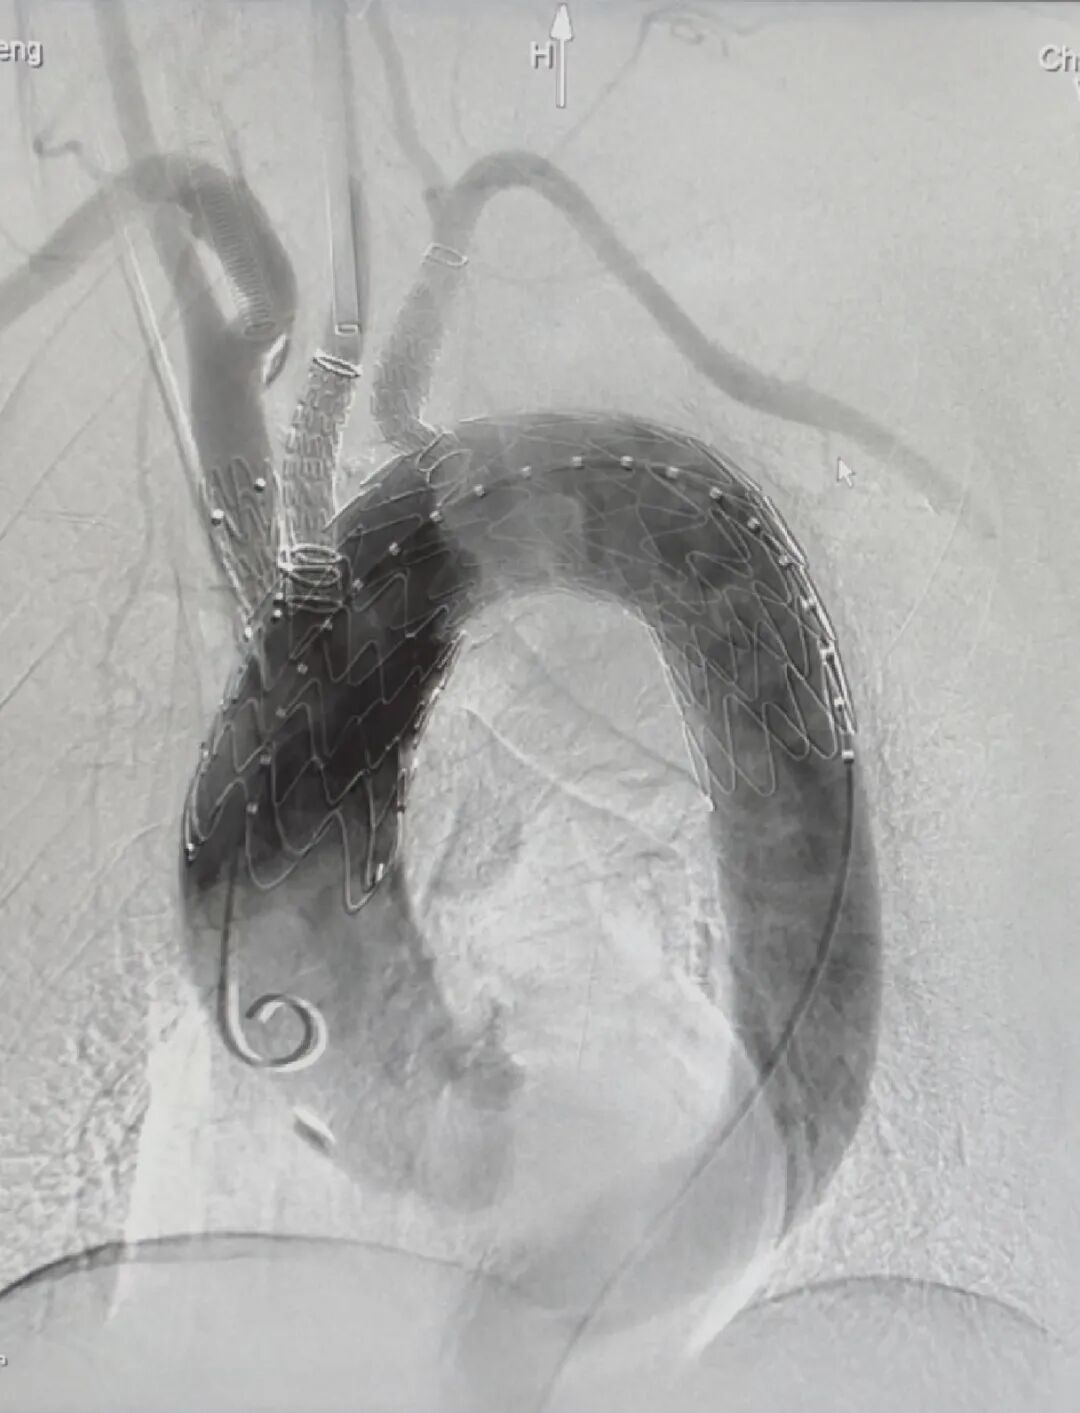

患者取仰卧位,解剖右侧股动脉和左颈总动脉,穿刺双侧肱动脉。造影显示主动脉弓部瘤,确认预期位置后,植入Hector?/通天戟?胸主多分支支架。术后造影显示:支架形态良好,定位精准;瘤体被完全隔绝,未见内漏;主动脉弓上三分支血流通畅,达到手术预期效果。

▲术后影像